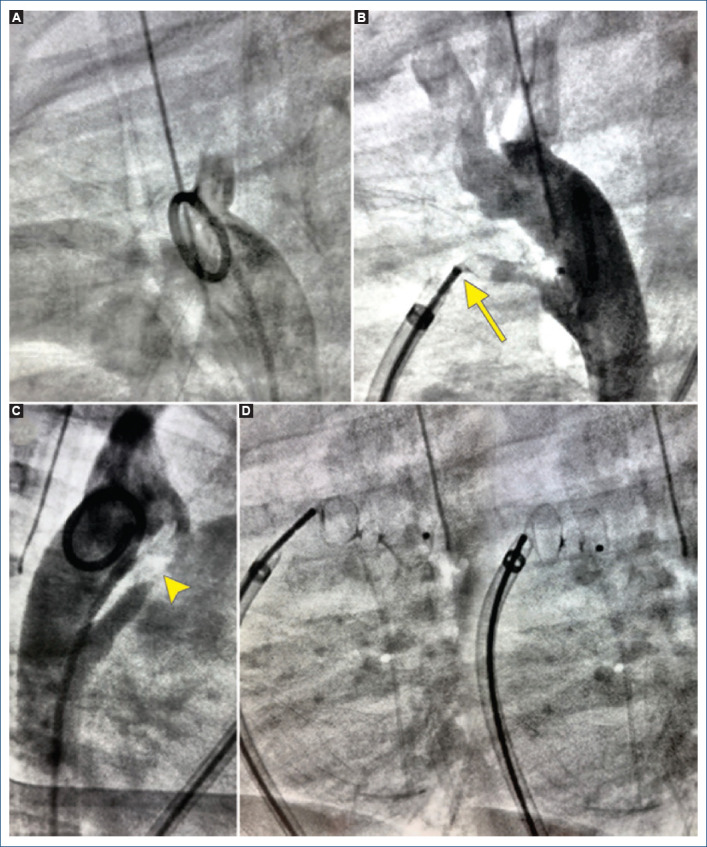

[Ductal spasm versus angiographic variations during patent ductus arteriosus transcatheter closure: case report].

{"title":"[Ductal spasm versus angiographic variations during patent ductus arteriosus transcatheter closure: case report].","authors":"Roberto Mijangos-Vázquez, Andrea Castillo-González","doi":"10.24875/ACM.24000104","DOIUrl":null,"url":null,"abstract":"","PeriodicalId":93885,"journal":{"name":"Archivos de cardiologia de Mexico","volume":" ","pages":"241-244"},"PeriodicalIF":0.0000,"publicationDate":"2025-02-19","publicationTypes":"Journal Article","fieldsOfStudy":null,"isOpenAccess":false,"openAccessPdf":"https://www.ncbi.nlm.nih.gov/pmc/articles/PMC12324848/pdf/","citationCount":"0","resultStr":null,"platform":"Semanticscholar","paperid":null,"PeriodicalName":"Archivos de cardiologia de Mexico","FirstCategoryId":"1085","ListUrlMain":"https://doi.org/10.24875/ACM.24000104","RegionNum":0,"RegionCategory":null,"ArticlePicture":[],"TitleCN":null,"AbstractTextCN":null,"PMCID":null,"EPubDate":"","PubModel":"","JCR":"","JCRName":"","Score":null,"Total":0}